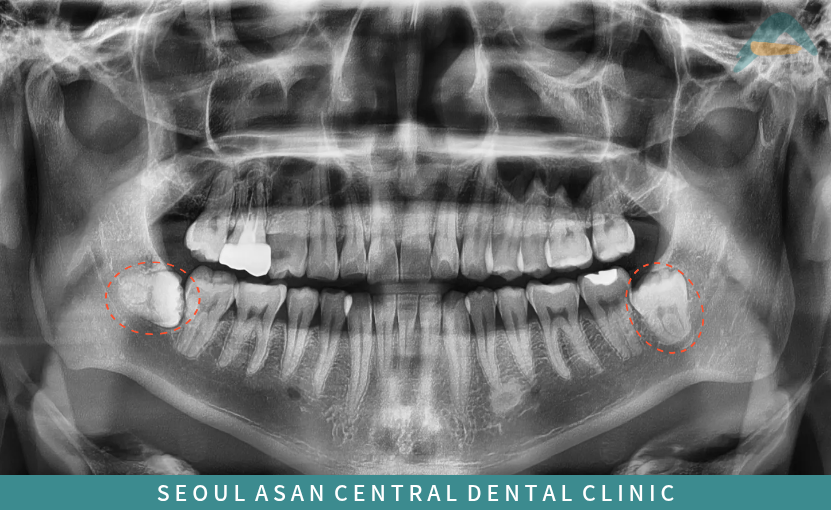

해당 파노라마 사진에서

보이는 것과 같이

아래턱 양측 사랑니가

모두 치아의 일부만 잇몸뼈 위로

맹출 되어 있는

반매복 상태의 형태를 보이고 있는데요.

이 경우 일부 드러나 있는 사랑니와

바로 앞의 어금니 사이에

음식물이 끼기 쉽고,

이로 인해 주변으로

충치와 염증 유발 가능성이 높아

이대로 방치하게 된다면

바로 앞의 어금니에도

충치가 생길 수 있어

치료의 범위가 커질 수 있기 때문에 수정구치과

의료진과 정밀한 검사와 상담을 통해

발치를 진행해 주는 것이 좋습니다.